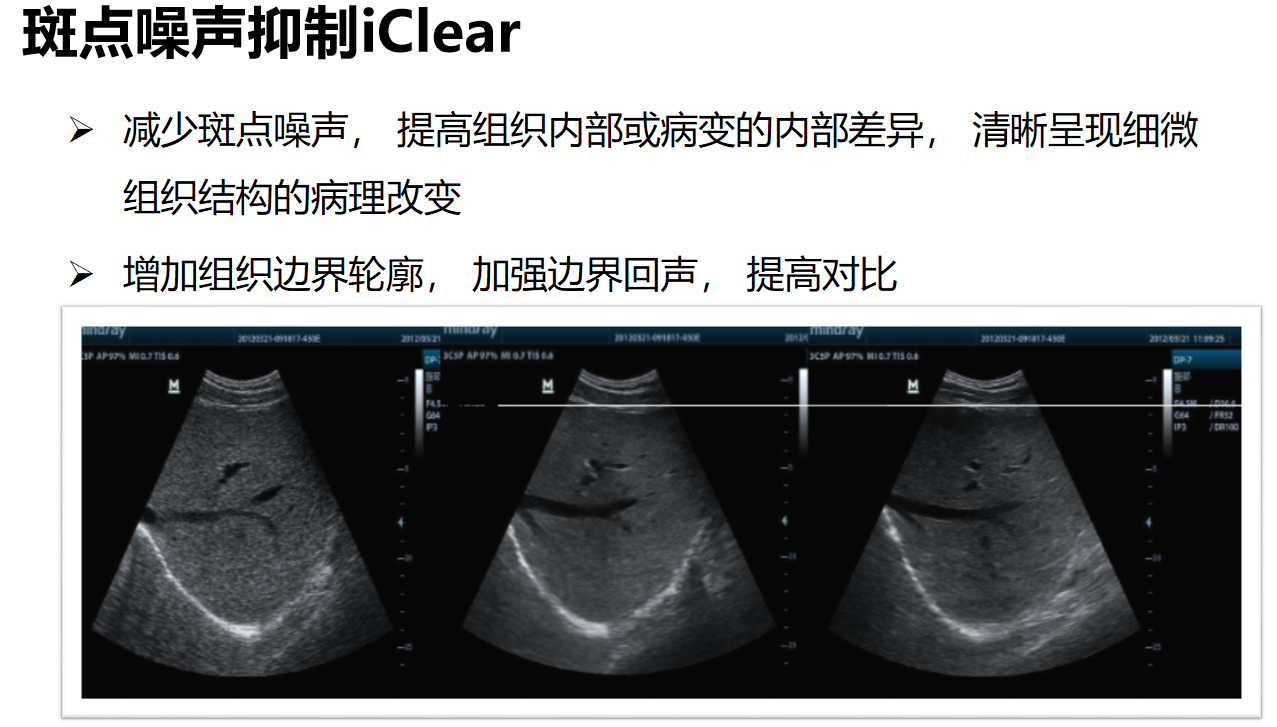

斑点噪声抑制iClear通过增强图像边界轮廓,提高对比度,以分辨图像的边界,来达到优化图像的目的。可以减少斑点噪声, 提高组织内部或病变的内部差异, 清晰呈现细微组织结构的病理改变